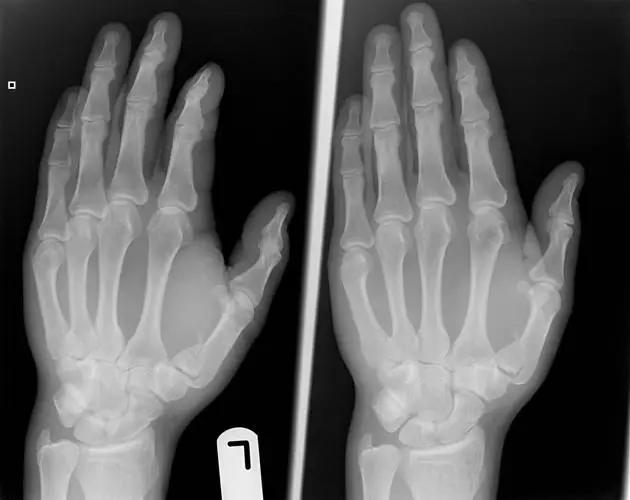

6. Bennett 骨折

第 1 掌骨基底的斜形骨折,掌骨近端形成轴向移位,掌侧边缘形成三角形的骨碎片。

(来源:Radiopaedia)

7. Boxer's 骨折

第 5 掌骨颈骨折伴有掌骨头向掌侧移位。